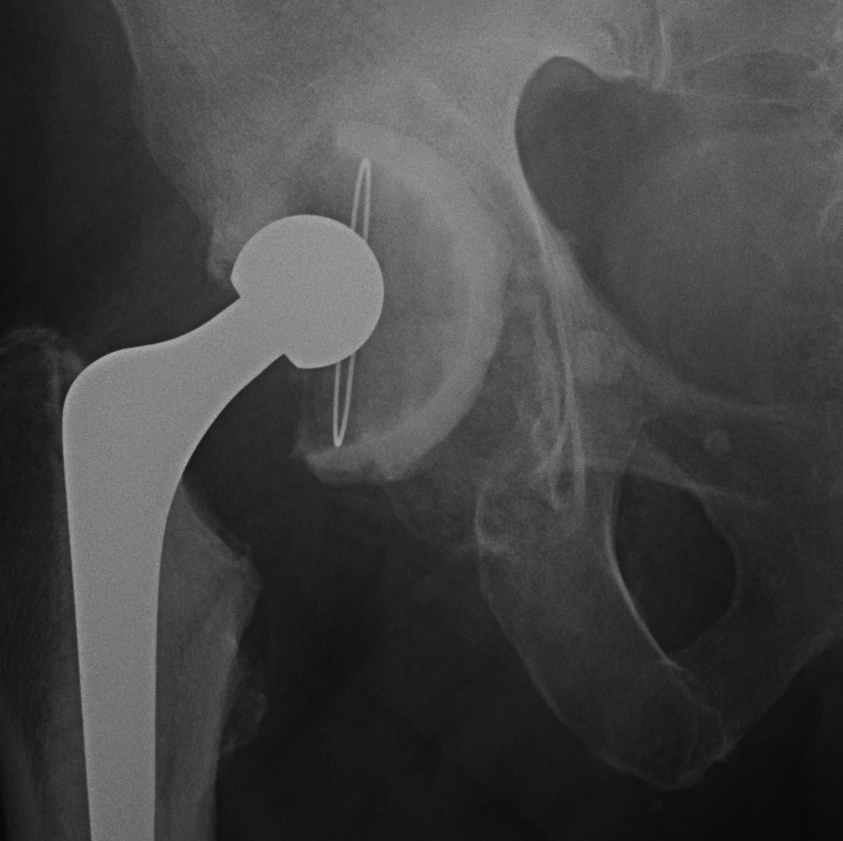

4. Bilobed uncemented acetabular components

Indications

- superolateral deficiency

- revision

- DDH cups

Problems

- can be difficult to get version right